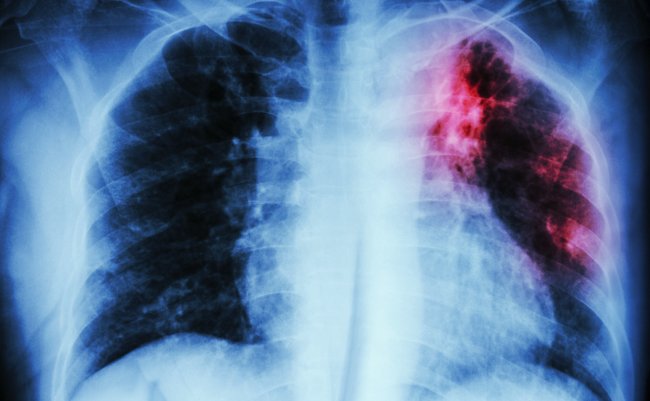

感染経路の多くは気道を通しての感染です。肺に感染することで肺結核となりますが、腎臓やリンパ節、骨、脳など、身体のあらゆる部分に影響が及ぶことがあります。

今回は、結核のうち8割以上を占める肺結核についてご紹介していこうと思います。

これらの症状を放っておき進行してしまうと、症状は重くなり、血痰(けったん)や喀血(かっけつ;肺や気管支などから出血して、口・鼻から出すこと)して呼吸困難に陥る場合もあります。肺結核の進行はゆっくりのため、深刻な症状が出て診察を受けた時には、すでに重症化していることが多いのです。

結核の感染を調べるには、「ツベルクリン反応検査」という皮下注射や、「インターフェロンガンマ遊離試験」という採血検査などによって診断できます。また、発病の有無は、X線を使った画像診断や痰の細菌検査で診断をします。